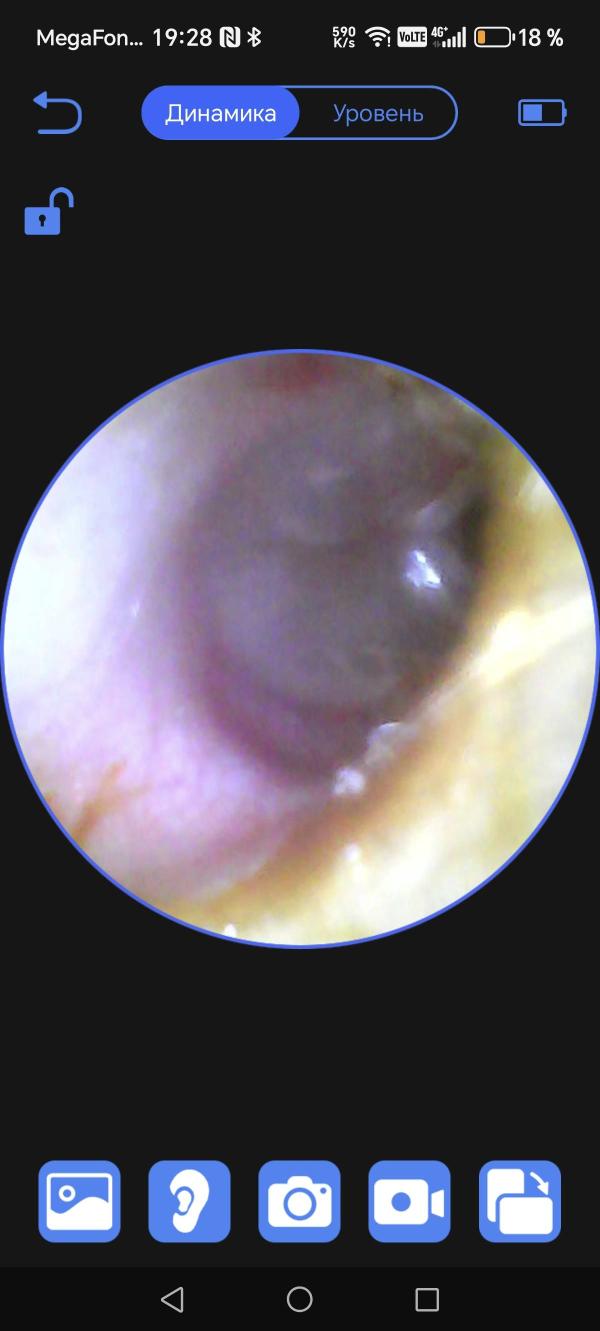

Есть кто разбирается в отитах? Есть фото барабанной перепонки. Ребёнок чешет уши, сопли. Температуры нет. К врачу пойдём уж, просто переживаю. Красное вокруг барабанной перепонки, но уши не болят.